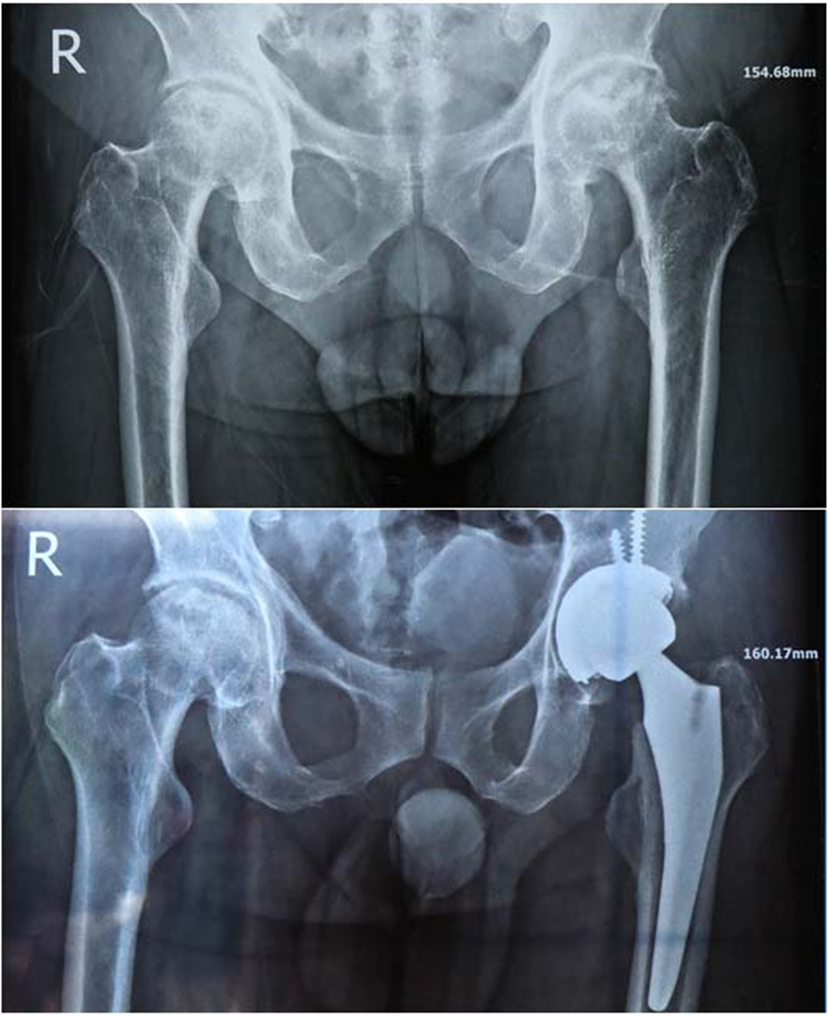

而手术机器人的加入,进一步增加的手术精准性和安全性。它可通过精准扫描,实时呈现患者髋关节的各项解剖结构数据,构建出精准的3D解剖模型,为医生提供清晰、直观的手术视野和精准的操作引导,让假体安放、髋臼打磨等关键手术步骤更精准、更规范,有效避免了传统手术中依赖医生经验可能出现的偏差。“术中,在机器人的辅助下,我们将髋臼角度精准调控至前倾15度左右、外展45度左右的最佳位置,术后患者双腿长度完全一致,关节活动度也达到了理想状态。”胡佩良院长补充道。